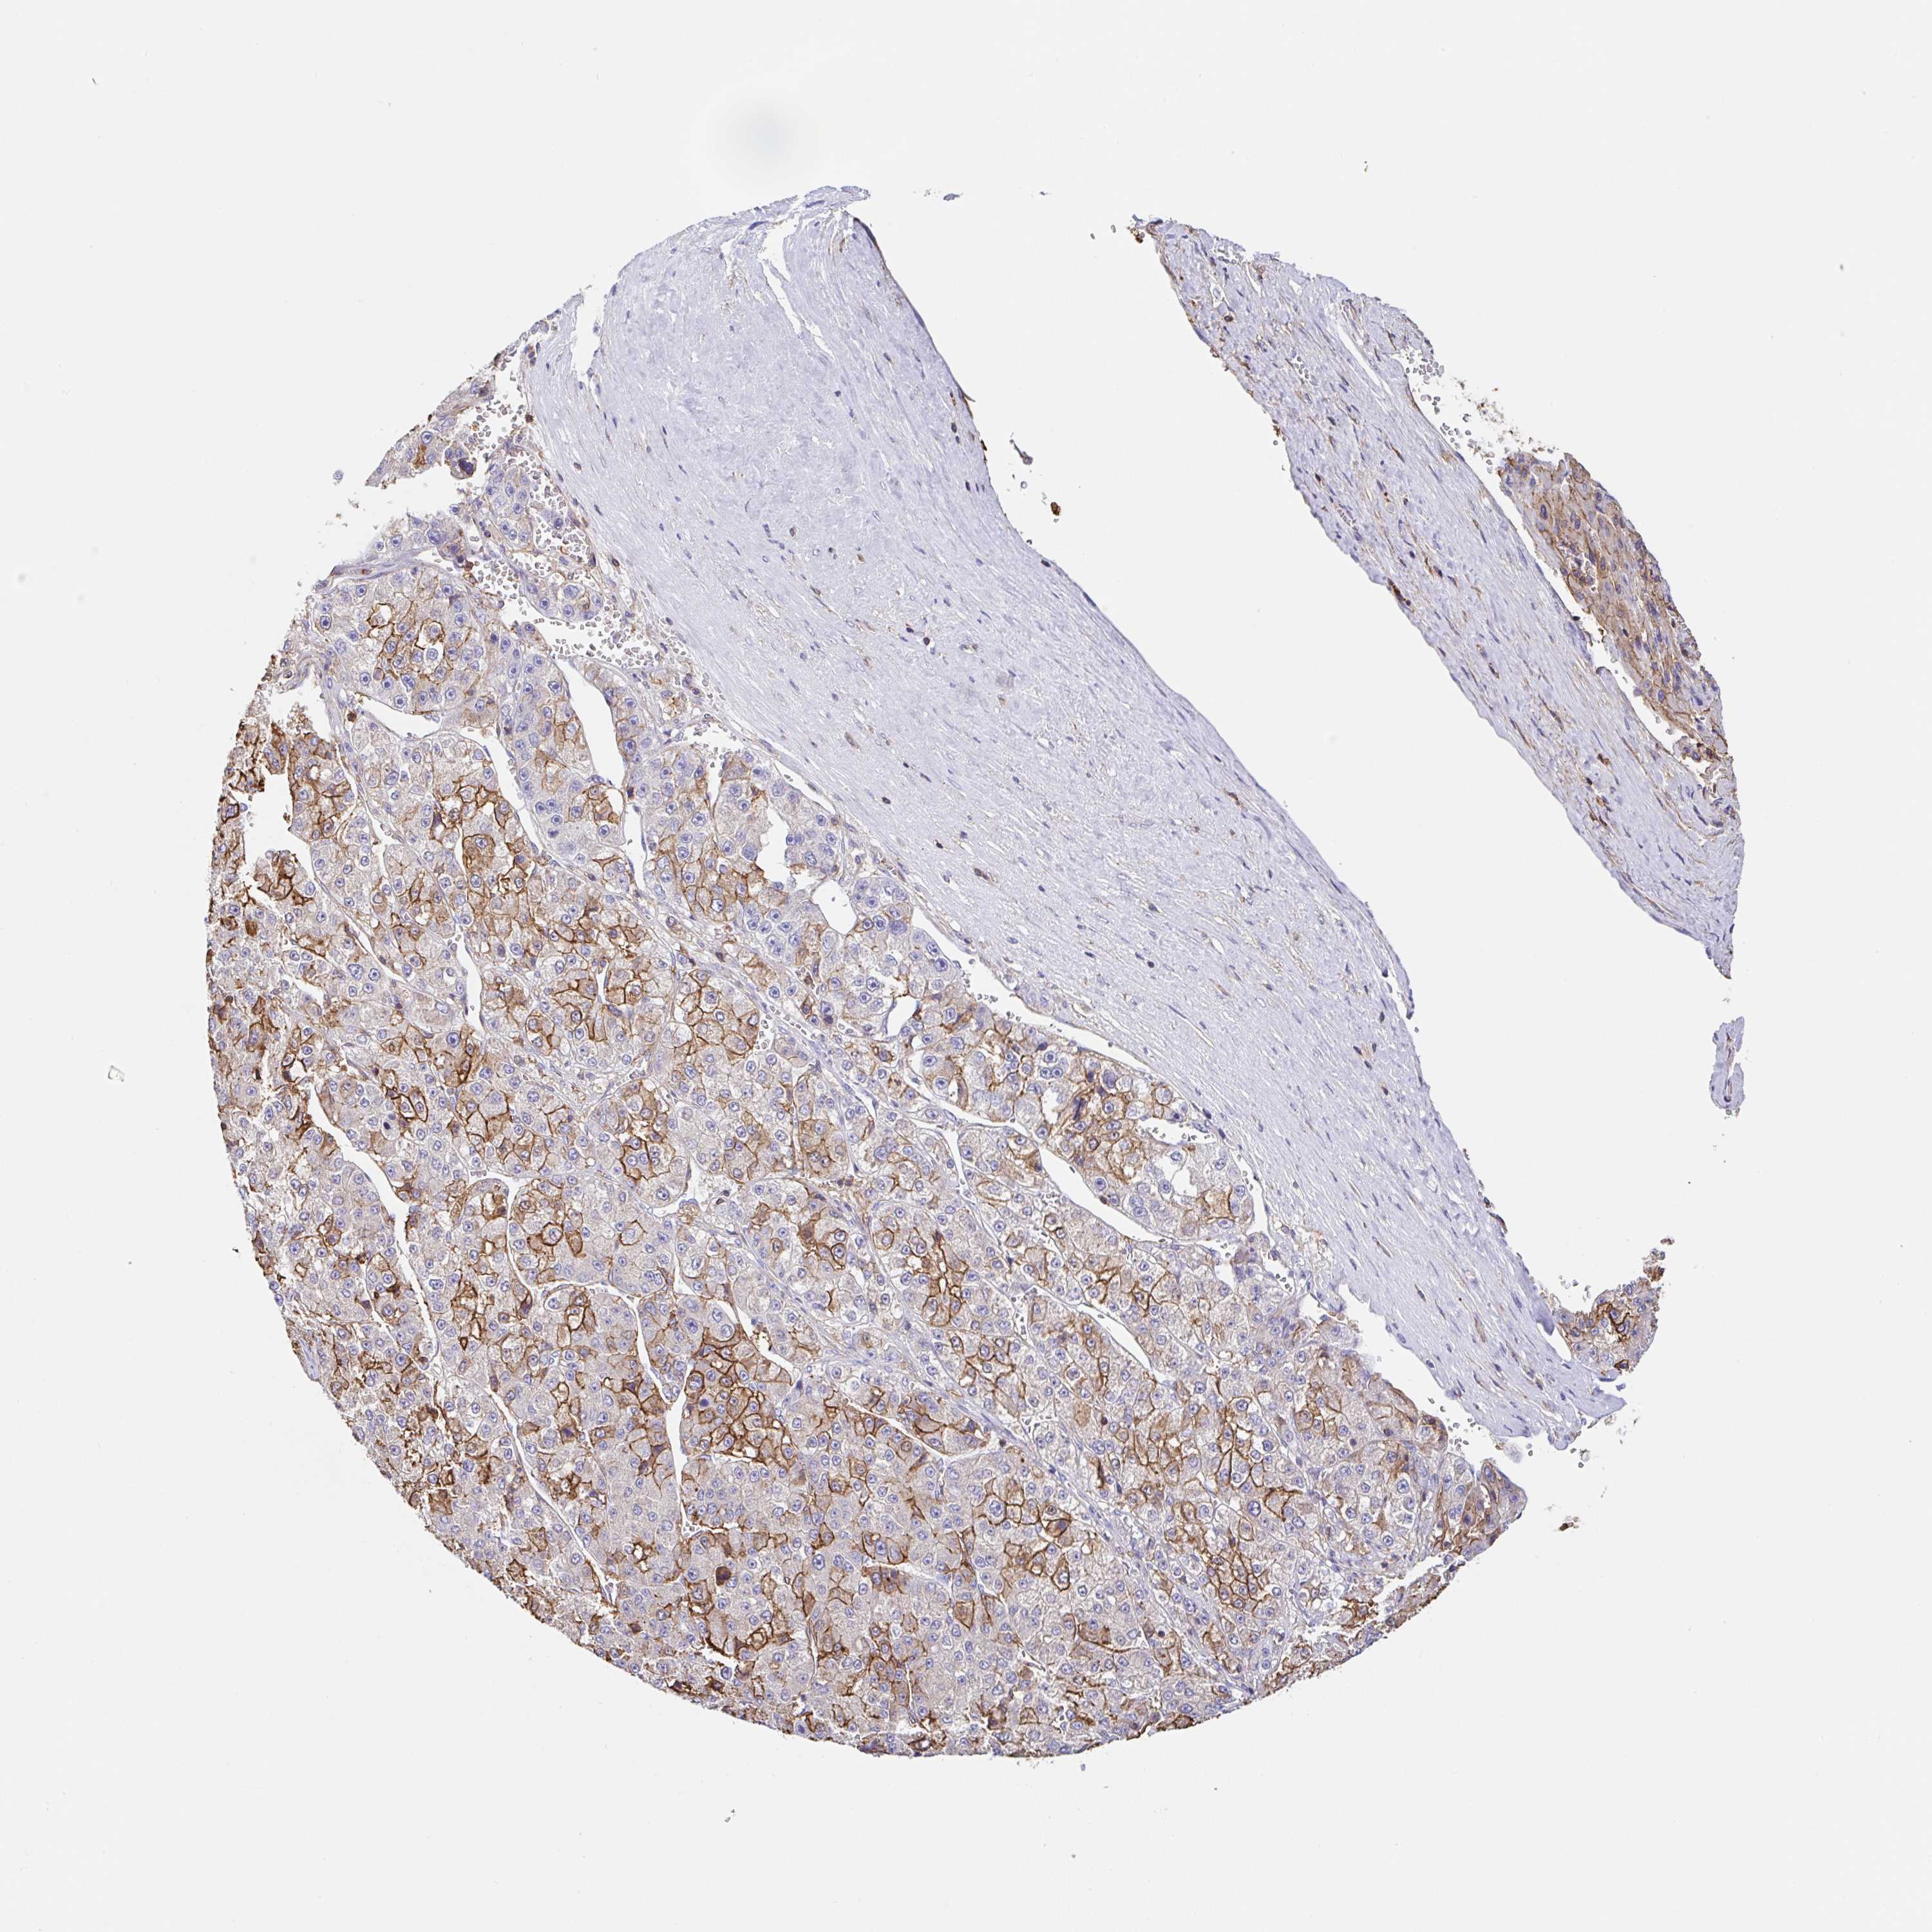

LIVER CANCER - Protein expressioni

A mouse-over function shows sample information and annotation data. Click on an image to view it in a full screen mode. Samples can be filtered based on level of antibody staining by selecting one or several of the following categories: high, medium, low and not detected. The assay and annotation is described here.

Note that samples used for immunohistochemistry by the Human Protein Atlas do not correspond to samples in the TCGA dataset.

Antibody stainingi

Antibody staining in the annotated cell types in the current human tissue is reported as not detected, low, medium, or high, based on conventional immunohistochemistry profiling in selected tissues. This score is based on the combination of the staining intensity and fraction of stained cells.

Each image is clickable and will lead to virtual microscopy that enables deeper exploration of all samples and also displays staining intensity scores, fraction scores and subcellular localization as well as patient and tissue information for each sample.

Antibody HPA054862

Staining

High

Medium

Low

Not detected

Intensity

Strong

Moderate

Weak

Negative

Quantity

>75%

75%-25%

<25%

None

Location

Nuclear

Cytoplasmic/membranous

Cytoplasmic/membranous,nuclear

Cholangiocarcinoma

Carcinoma, Hepatocellular, NOS